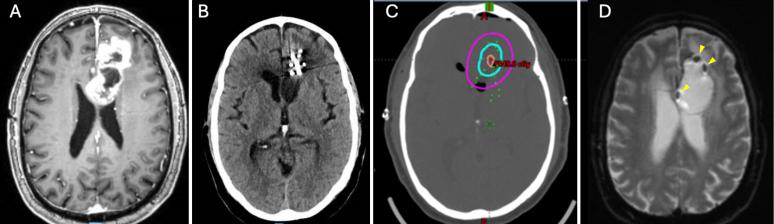

Reirradiation of recurrent high-grade gliomas (HGGs) with external beam radiation therapy is limited by the risk of radiation necrosis (RN). Intraoperative brachytherapy offers a localized radiation approach that minimizes RN risk while maintaining tumor control. However, seed migration has historically limited its use in periventricular regions. The authors present 3 cases of recurrent periventricular HGG (2 IDH-wildtype, MGMT promoter-methylated, EGFR-amplified WHO grade 4 glioblastoma and 1 WHO grade 3 astrocytoma) in which a three-layered barrier was created between the ventricular lining and tumor cavity to prevent seed migration, enabling successful brachytherapy.

OBSERVATIONS

Following maximal safe resection, a three-layered patch separated the resection cavity from the ventricle prior to cesium-131 (131Cs) brachytherapy. Patient 1 received suture-stranded 131Cs (20 seeds), while patients 2 and 3 received 131Cs GammaTile (6 tiles, 4 seeds per tile). A three-layered barrier was formed using Gelfoam, Surgicel, and Adherus. At a median 22-month (range 11-24 months) follow-up, MRI confirmed no seed migration and seeds remained in the cavity. There were no complications associated with the barrier placement.